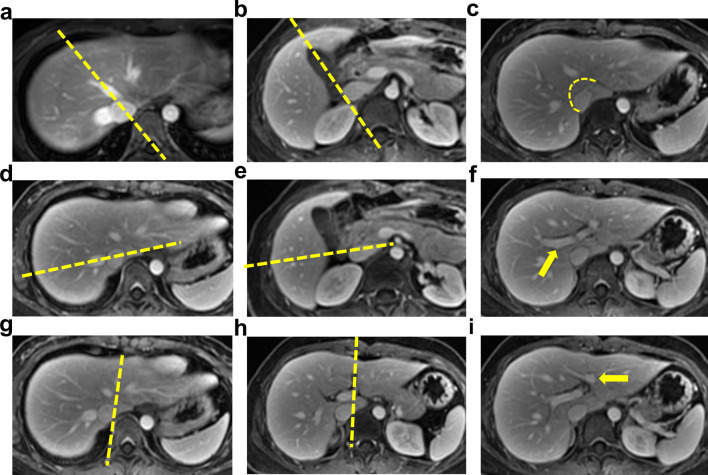

Fig. 1.

Method of Couinaud’s classification on axial MRI images. Five planes (three vertical planes along the main stem of hepatic veins and two horizontal planes through the primary branches of the portal vein) are used to divide the liver. In axial MR images, the line from the midpoint of the IVC to the MHV or vertex of the gallbladder fossa divides the right and left lobes (a and b). The RHV further divides the right lobe into anterior and posterior segments (d and e). The LHV (in the upper part of the liver) and the left longitudinal fissure (in the lower part of the liver) divide the left lobe into a medial and a lateral segment. (g and h). Each segment of right and left lateral lobes is further divided into a superior segment and an inferior segment by the main stem of the right portal vein and the sagittal part of the left portal vein (f and i). The caudate lobe is separated from the other segments by the natural curve from the venous ligament fissure to the right wall of the IVC (c). IVC, inferior vena cava; MHV, middle hepatic vein; RHV, right hepatic vein; LHV, left hepatic vein.